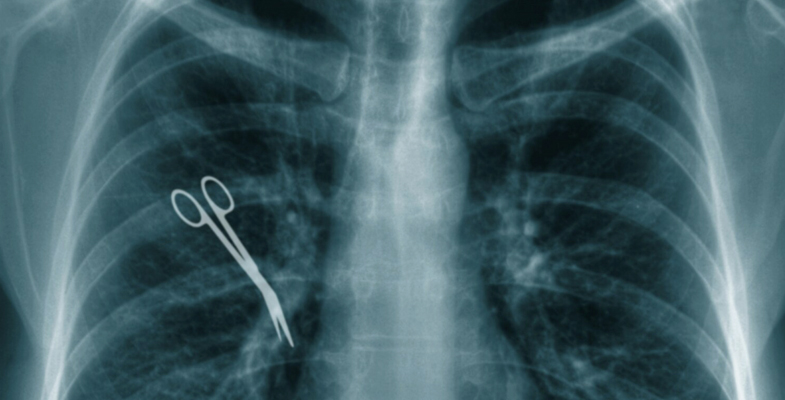

- Foreign Objects Left in the Body